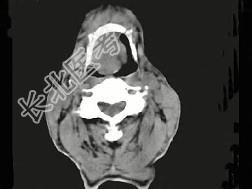

- 单项选择题男,74岁, 咽喉部不适一年余,近两三个月咽喉疼痛, 吞咽困难,CT如图所示, 最可能诊断是  (    )

- A、喉癌

- B、会厌癌

- C、声带癌

- D、声门下区癌

- E、跨声门型癌